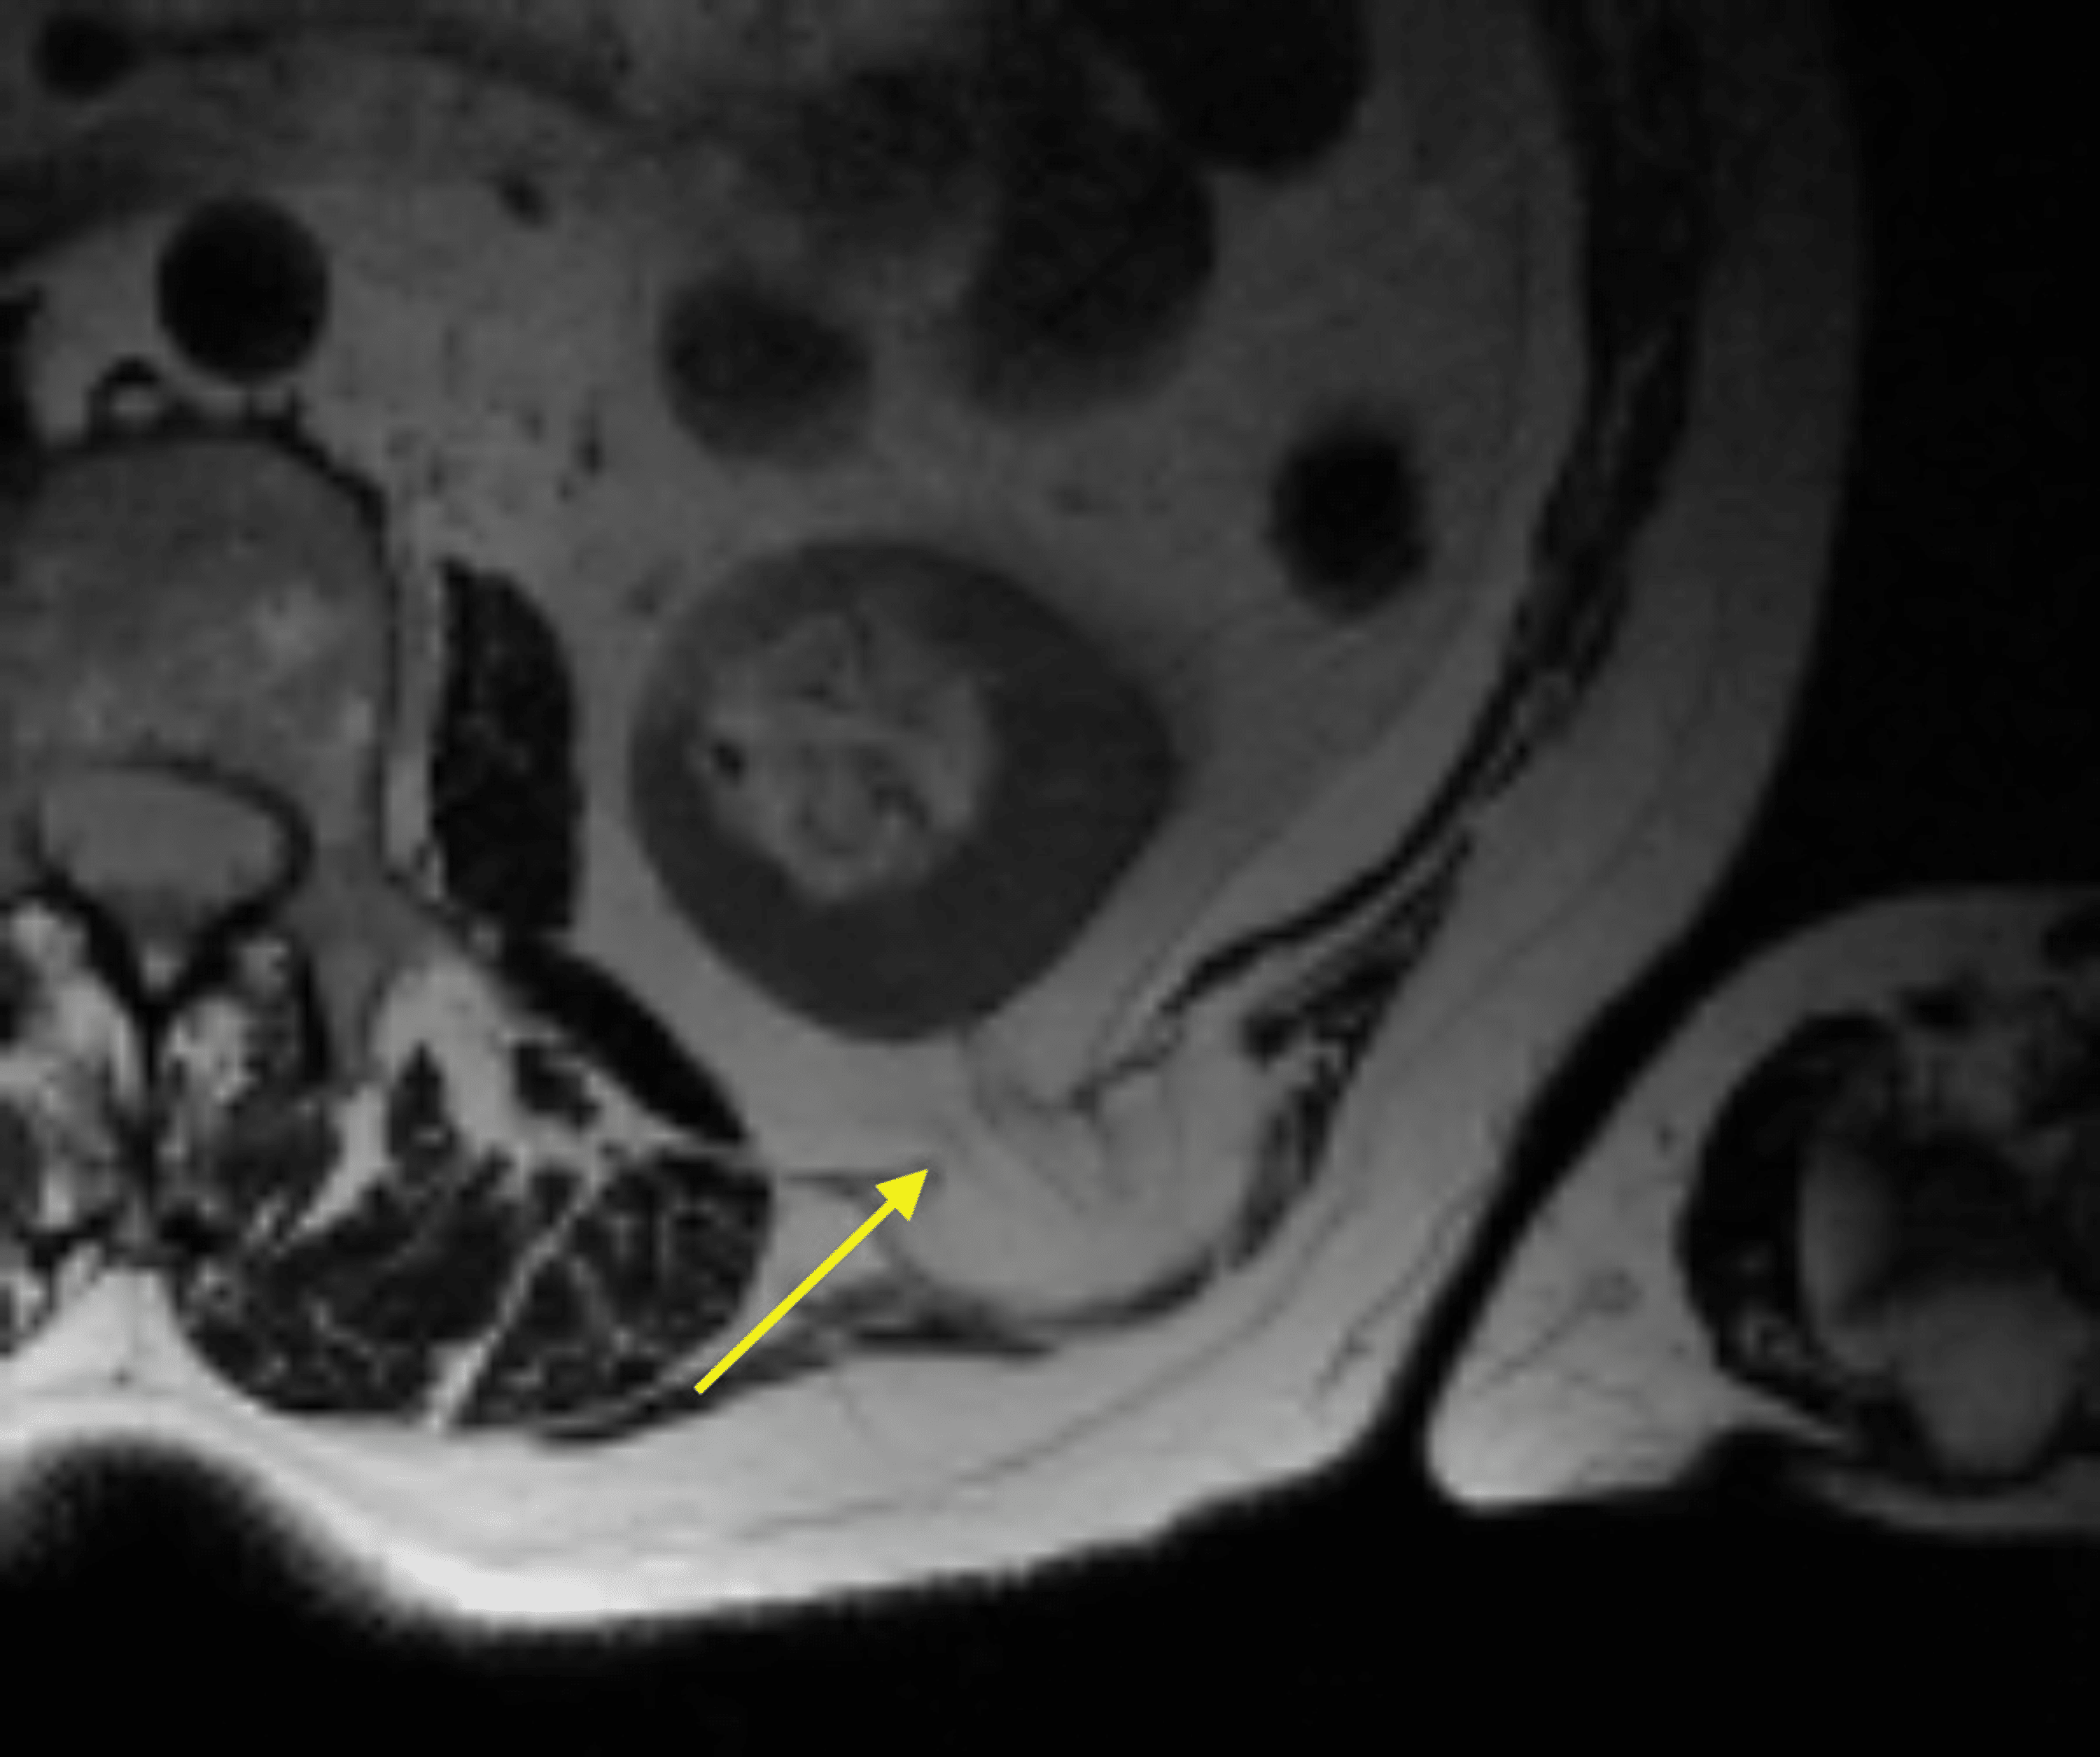

From www.cureus.com

Cureus A Case of an Atraumatic Posterior Perirenal Lumbar Hernia Lumbar Hernia Reddit Calisthenics is all i have left lol. I got diagnosed with 3 herniated discs in my lumbar spine and lumbar degenerative disc disease. Patients with lumbar hernias can present with a variety of symptoms, including a posterolateral mass, back pain, bowel obstruction (if contents. I herniated my disc in a cave problem years ago (l5s1) and it wasn’t properly diagnosed. Lumbar Hernia Reddit.